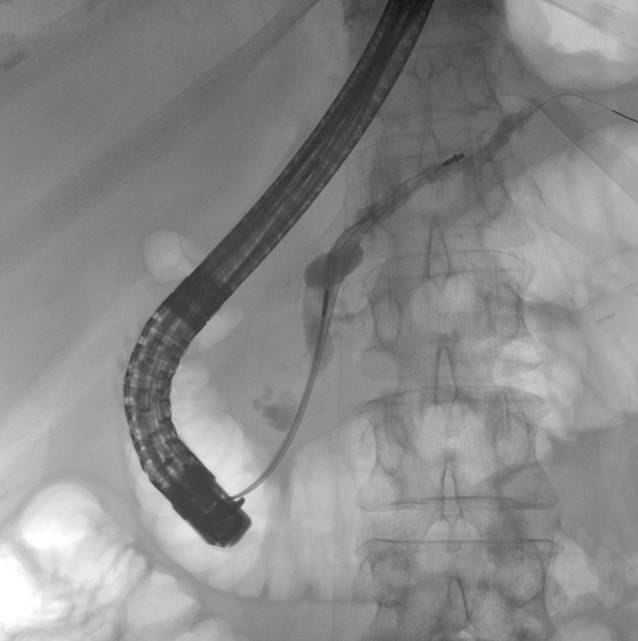

Zuletzt wurde im ESCAPE-Trial die Überlegenheit der chirurgischen Therapie bei Patienten mit kurzzeitiger Opioidtherapie und einem erweiterten Ductus pancreaticus über 5 mm gegenüber der endoskopischen Therapie im Sinn einer besseren Schmerzkontrolle nachgewiesen [22]. Damit ist die operative Sanierung für symptomatische Pankreasgangstenosen mit seit Kurzem bestehender Opioidpflichtigkeit indiziert. Da sie jedoch mit einer höheren Letalität vergesellschaftet ist, kann auch initial ein 3‑monatiges Stenting des Pankreasgangs erfolgen; bei fehlender Besserung (Evaluierung nach 6 bis 8 Wochen) ist die operative Sanierung erneut in Betracht zu ziehen [1, 15]. Die Operation zeigt sich auch bei rezidivierenden, symptomatischen Pankreasgangsteinen der endoskopischen Therapie überlegen [1]. Symptomatische Pseudozysten sollten primär endoskopisch und je nach Lokalisation und Größe transpapillär oder endosonographisch gezielt transmural abgeleitet werden. Bei Rezidiven kann eine chirurgische Sanierung erfolgen. Auch bei einer biliären Stenose steht die endoskopische Versorgung mittels 12-monatigem Stentingprogramm im Vordergrund (Abb. 3). Die chirurgische Sanierung ist nach Therapieversagen indiziert. Das Stenting erfolgt bei Gallengang- und Pankreasgangstenosen mit Plastikstents oder fcSEMS („fully covered self-expanding metal stents“; [1, 15]). Mittels neuer Generationen von biodegradablen Stents lässt sich die Anzahl der Interventionen bei einem Stentingprogramm von pankreatischen oder biliären Stenosen potenziell verringern (Abb. 4a, b). Langzeitdaten hinsichtlich des Nebenwirkungsprofils sowie der Kosten-Nutzen-Effizienz liegen allerdings noch nicht vor. Eingeblutete Pseudozysten sowie Pseudoaneurysmata sind primär einer angiographischen Intervention zuzuweisen [4].

Abb. 4

a Abgesetzter biodegradabler Stent im Rahmen eines Stentingprogramms bei chronischer Pankreatitis, b Pankreaskopfpankreatits mit Hauptgangstenose und nachgeschalteter Erweiterung